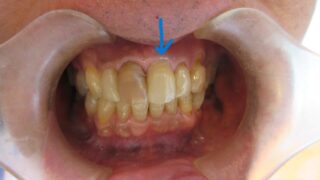

差し歯

折れてしまった歯をオールセラミックで仕上げました。反対側はブリーチングで白くする予定です。